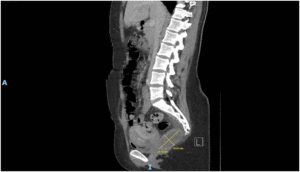

Imaging via MRI and CT demonstrated a complex, encapsulated lesion with peripheral enhancement and restricted diffusion. Multidisciplinary evaluation suggested a congenital epidermoid or duplication cyst. Given the absence of malignancy and surgical complexity, a conservative management strategy was adopted.

Figure 4: Figure 4 Duplication cyst 2020 sagittal plane